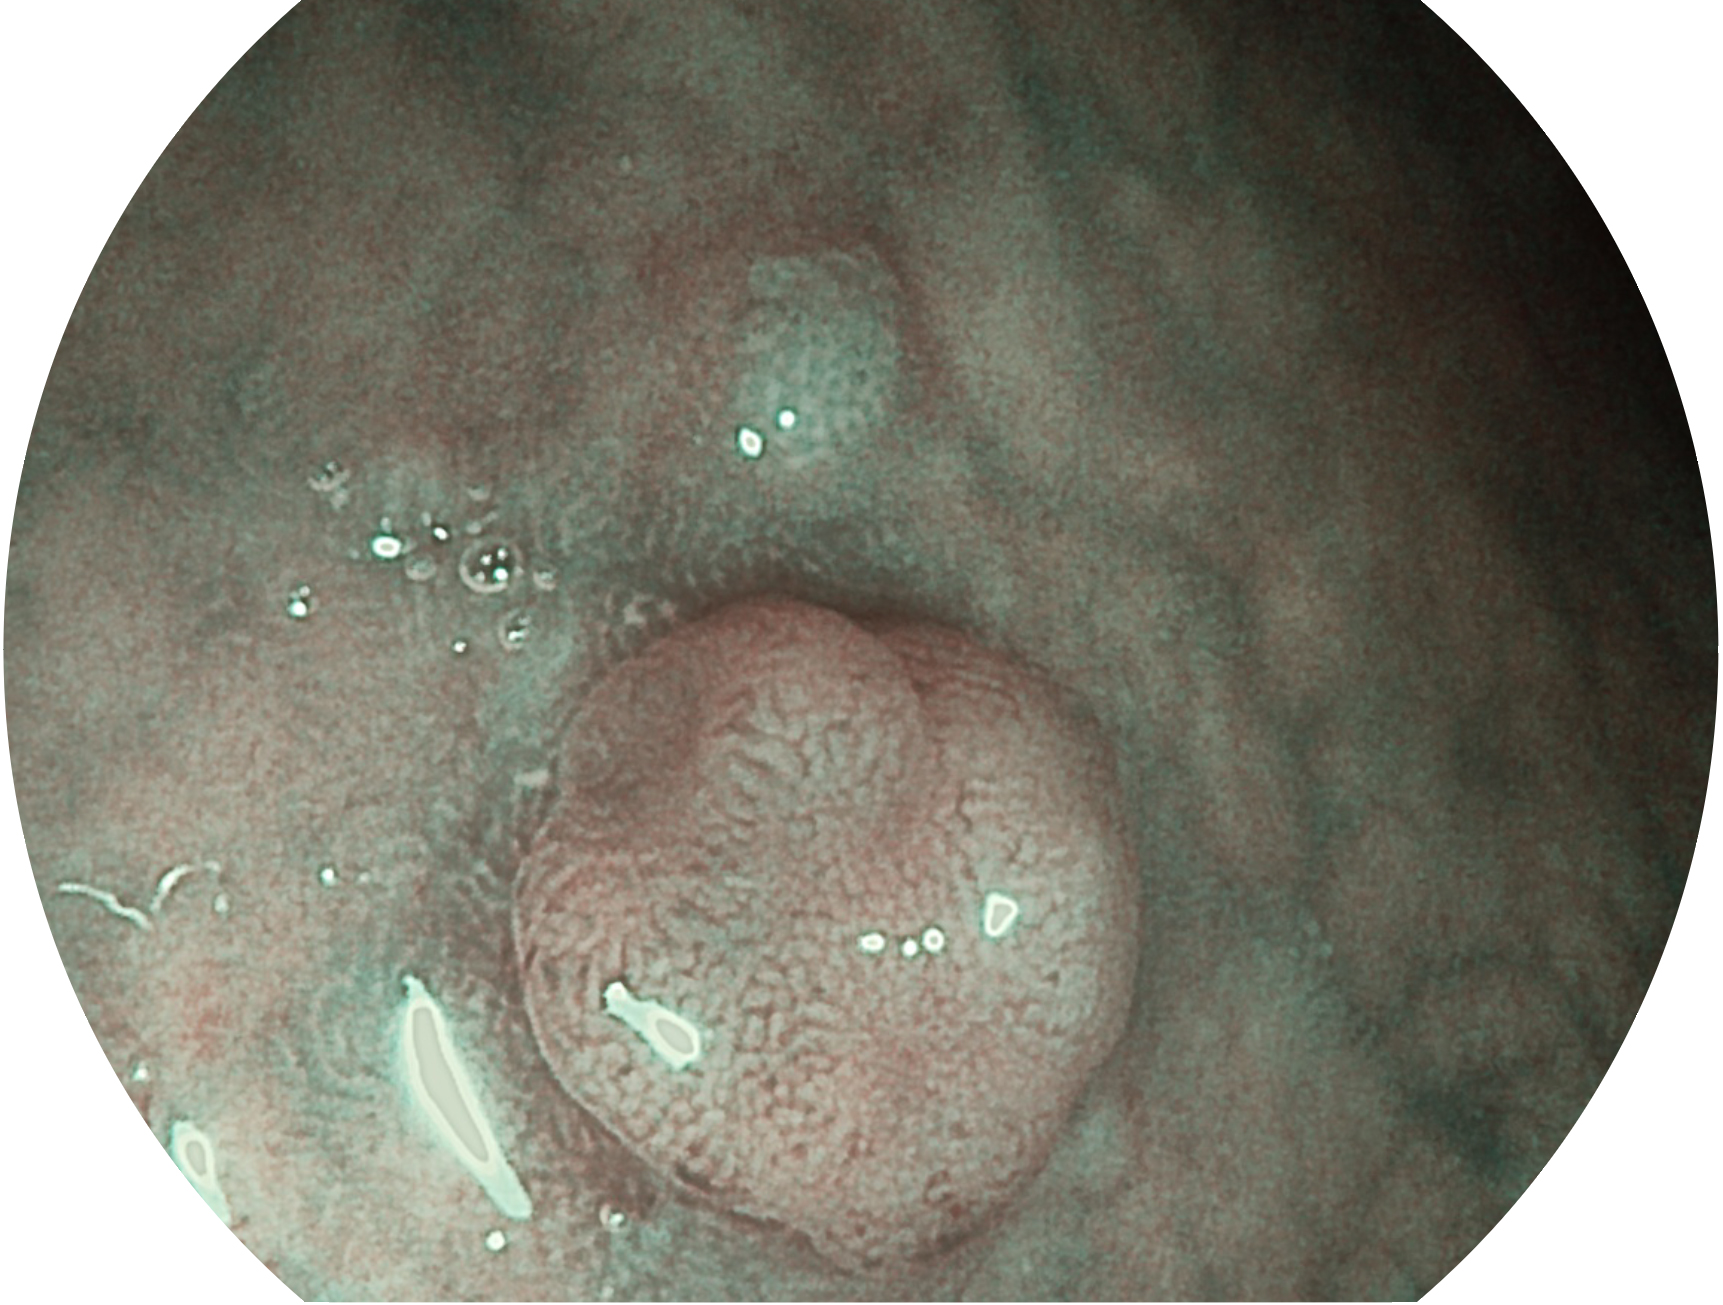

哈哈体育官网新开发的内镜染色技术,主要是基于多波长LED 光源的开发,VLS-55Q 四波长LED 光源是由四个不同颜色的LED光按照相应照明模式所规定的特定发光比例进行合束后形成,合束后形成的照明光的光谱由红光、绿光、蓝光及蓝紫光这四个不同的波段范围构成。具有更高光谱自由度,通过光谱比例的控制,实现了聚谱成像技术,英文全称为“Spectral Focused Imaging, SFI”,缩写为“SFI”和光电复合染色成像技术,英文全称为“Versatile Intelligent Staining Technology, VIST”,缩写为“VIST”。